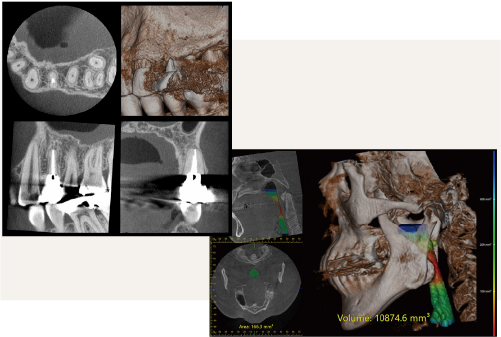

インプラント

※ 価格は全て税込です